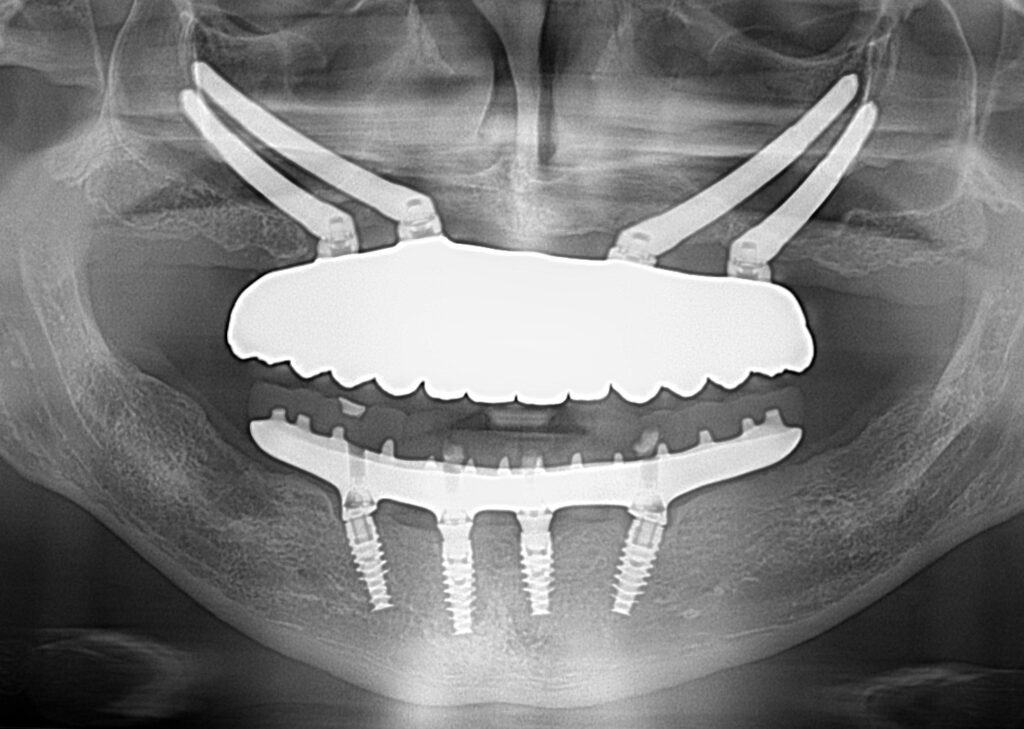

A selection of full arch fixed implant bridge patients after 5 years of wear